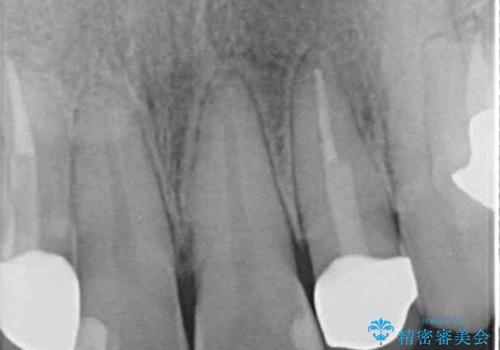

- 前歯の歯並びと神経を取って変色してしまった前歯を気にして来院された患者様です。

上下前歯の歯列不正はインビザラインにより整え、その後に、前歯2本をオールセラミッククラウンにて補綴治療することとしました。

下顎前歯が1本欠損しており、下顎歯列の大きさが本来よりも小さいため、上顎歯列とのバランスが悪く、深い咬み合わせになっていました。

上顎にIPRを多用して歯列の大きさを小さくするよう試みましたが、理想的な咬み合わせまでには改善させることはできませんでした。